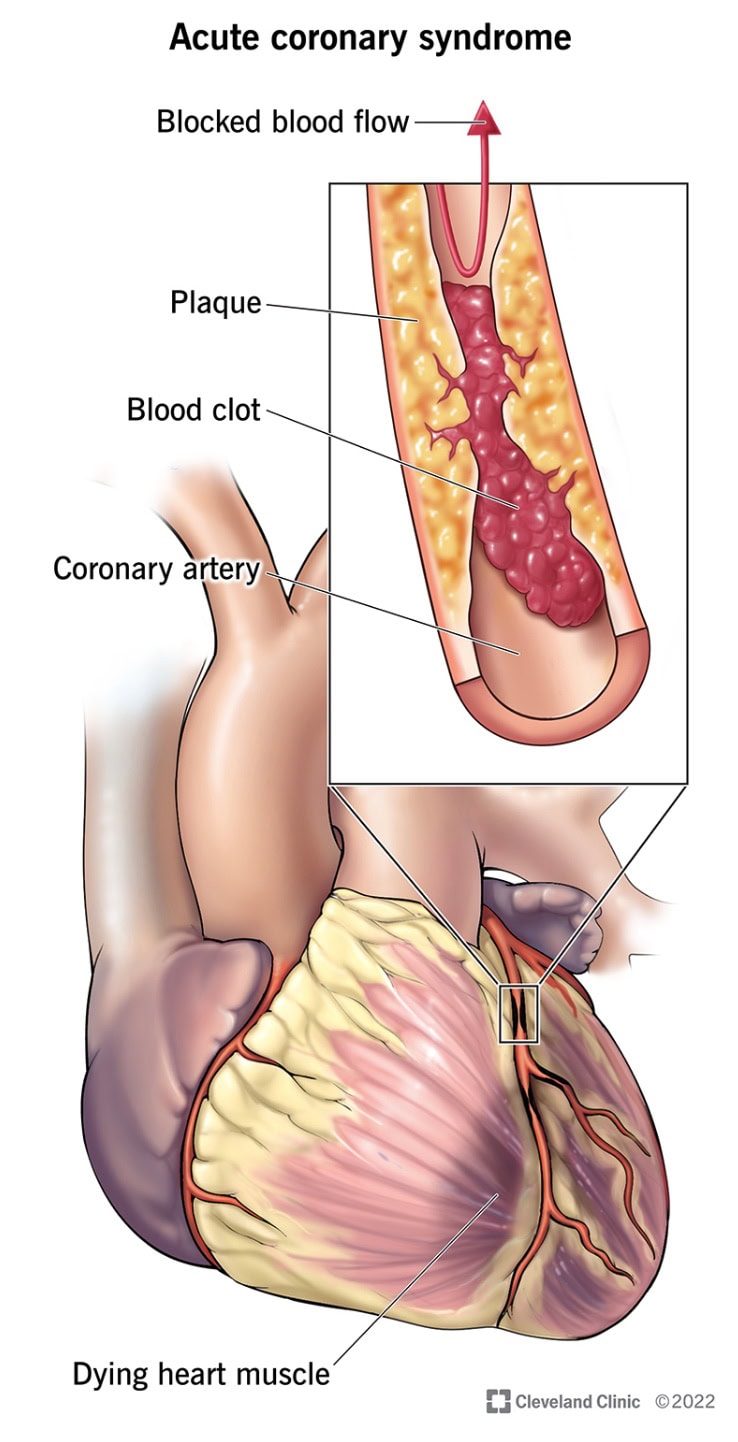

Pathomechanismus

ACS wird häufig durch das Zerreißen eines Plaques in einer Koronararterie verursacht, was zur Bildung eines Blutgerinnsels führt, das den Blutfluss teilweise oder vollständig blockiert.

- Instabile Angina pectoris: Dies ist der Fall, wenn der Schmerz oder das Unbehagen in der Brust unvorhersehbar ist und in Ruhe oder bei geringer Anstrengung auftritt. Es ist ein Warnzeichen für einen möglichen Herzinfarkt, ohne dass der Herzmuskel signifikant geschädigt ist.

- Non-ST-Elevation Myokardinfarkt (NSTEMI): Bei dieser Art von Herzinfarkt ist die Arterie teilweise blockiert, was zu einem verminderten Blutfluss und einer Schädigung eines Teils des Herzmuskels führt. Er führt jedoch nicht zu den spezifischen Veränderungen im Elektrokardiogramm (EKG), die bei einem ausgewachsenen Herzinfarkt (STEMI) zu beobachten sind.

- ST-Elevation Myokardinfarkt (STEMI): Dies ist die schwerste Form des Herzinfarkts, bei der eine Koronararterie vollständig blockiert ist. Sie führt zu einer erheblichen Schädigung des Herzmuskels und zeigt spezifische Veränderungen im EKG. Eine Notfallbehandlung ist erforderlich, um den Blutfluss wiederherzustellen.